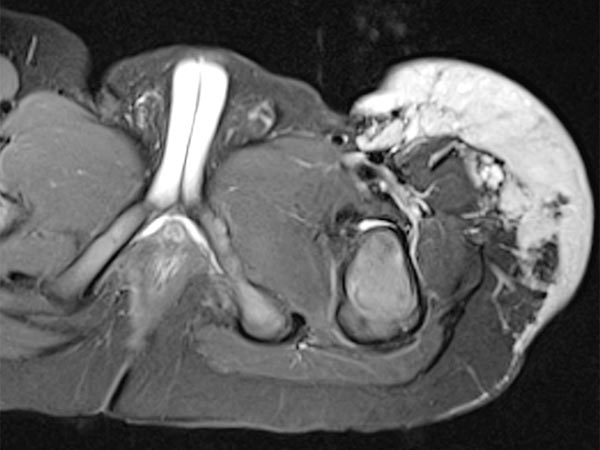

Coronal T2-weighted, fat-saturated MRI shows the tumor in the left groin as homogeneous and highly hyperintense (13 months of age) and clearly solid. Incidental findings include the soaked diaper, also with high signal intensity.

Same MRI sequence, coronal slice. The tumor is not only epifascial, but also shows a small subfascial extension under the fascia lata into the gluteal muscles. Thus, clearly infiltrative behavior.

Axial slice of MRI (T2-weighted, fat-saturated) also clearly shows the infiltration of the musculature by the mass. Hemangiomas as vascular tumors can also exhibit such infiltration without necessarily being malignant.